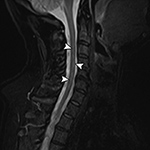

Truncation Artifact. (A) Sagittal STIR MR image demonstrates T2 hyperintense line (arrowheads) within the anterior spinal cord due to spinal-cord CSF interface

Truncation Artifact. (B) Corresponding axial MEDIC (multi-echo data image combination) MR image demonstrates normal appearance of the spinal cord.